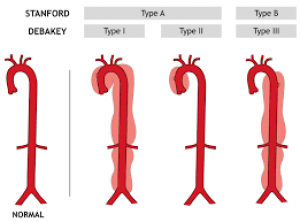

I.Đại cương:

- Phình tách động mạch chủ (PTĐMC) là hiện tượng lớp áo trong bị rách làm cho dòng máu bóc tách lớp áo giữa của thành động mạch. Đây là một cấp cứu nội khoa – ngoại khoa với tỷ lệ hiện mắc khoảng 5-30 ca/triệu người/năm), tần suất thay đổi phụ thuộc vào từng quần thể với các yếu tố nguy cơ khác nhau.